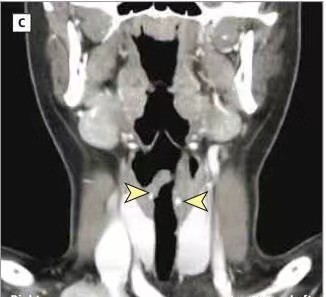

5.咽喉头颈部肿瘤:

喉乳头状瘤、喉部血管瘤、喉癌、甲状腺肿瘤等。